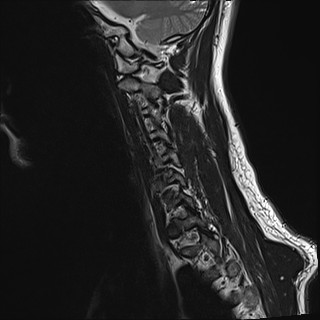

Wirbelsäule HWS

t2_tse_sag